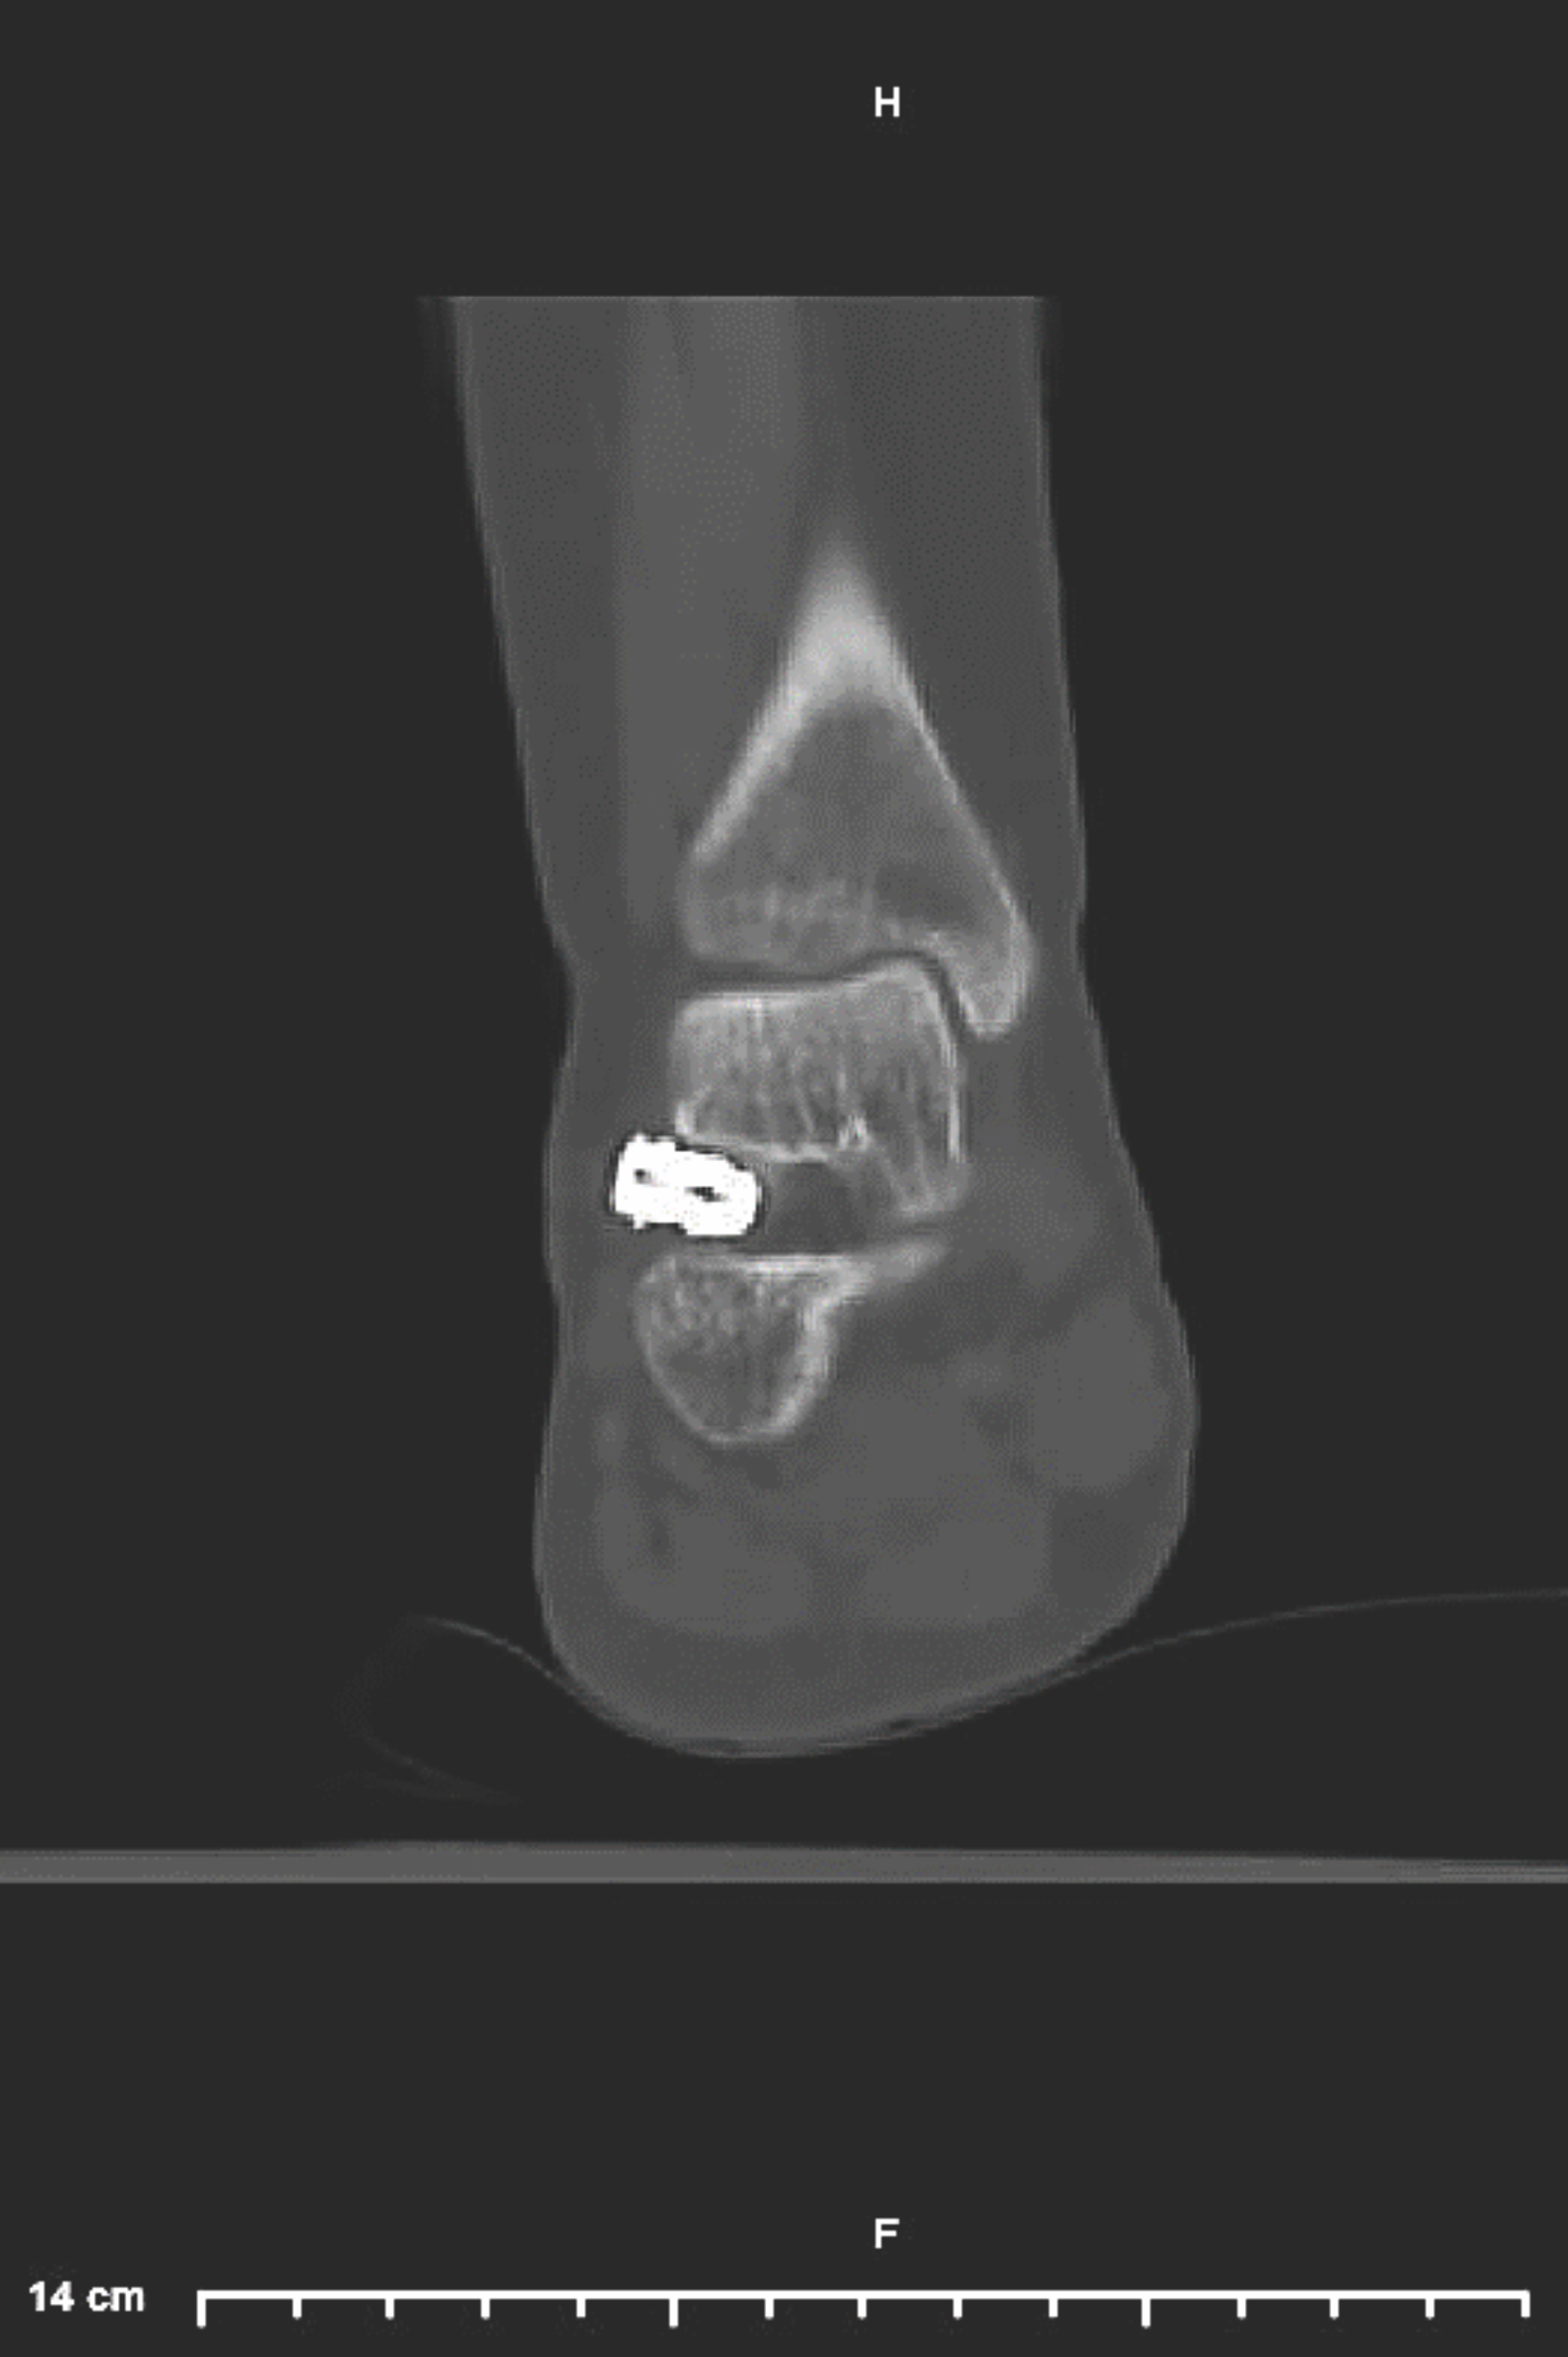

Blunt dissection should extend down into the sinus tarsi. For self-locking implants, a blunt probe can help to find the tunnel direction, and progressive size implant trials determine appropriate implant selection. After determining the appropriately sized implant, the hindfoot supinates into the corrected position, and the surgeon places the implant and checks it under fluoroscopy. For impact-blocking devices, one will then place a guidewire into the talus in a retrograde fashion, or into the calcaneus in an antegrade fashion. Next, using a drill over the guidewire will allow placement of a screw or implant device.1,3

The complications for subtalar arthroeresis fall into 4 main categories, which include inappropriate procedural selection, surgeon technical error, adaptation/irritation, and failure of the implant (Figures 1–2).3

The most common complication is persistent sinus tarsi pain, which requires implant removal in approximately 10–40% of patients.9 Fortunately, implant removal nearly completely alleviates the pain, and research has shown that the correction maintains over time.3,6 Inappropriate implant sizing may also necessitate implant removal due to over- or undercorrection of the deformity.9 Cook and colleagues retrospectively reviewed patients requiring arthroereisis explanation, finding that removal was often associated with smaller implant sizing.7 The smaller implant led to undercorrection with persistent pronation and residual deformity.7 The literature is limited regarding complication rates, and higher quality studies are needed to determine the true risk/benefit for arthroereisis implantation.